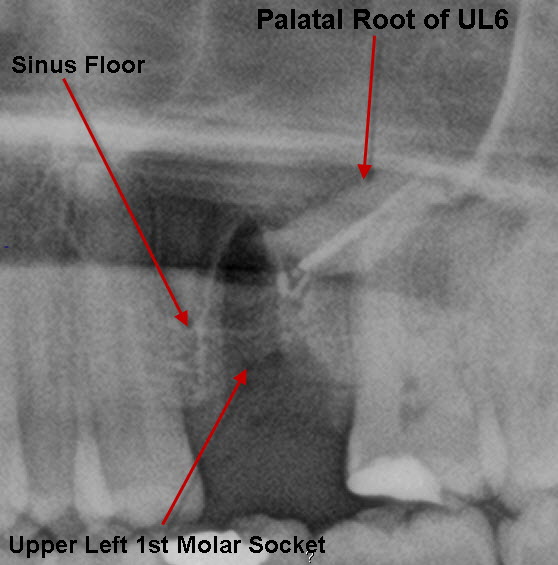

Mouth-Sinus Communications.

Mouth-Sinus Communications. Upper molar and premolar teeth often have their roots in close proximity to the sinus. In removing these teeth, there is a chance that a ‘hole’ can be made between the mouth & the sinus (this is sometimes not evident at the time of operation but may develop several weeks afterwards). If this ’hole’ persists or is left un-repaired, every time you drink, fluid can come out of the nose and you may develop a marked sinusitis. This ‘hole’ if small enough, can spontaneously close. It can be assisted in this by ‘cover plates’ that prevents food & fluids going into the sinus allowing the hole to close naturally. However, ‘holes’ above a certain size need to be surgically closed.